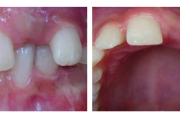

Ravijärgne seis. Jäävhammas on täielikult lõikunud.

) Röntgenülesvõte. Ülemise esimese jäävmolaari lõikumine on takistatud 2. piimamolaari tõttu

Esimese jäävmolaari ektoopiline lõikumine